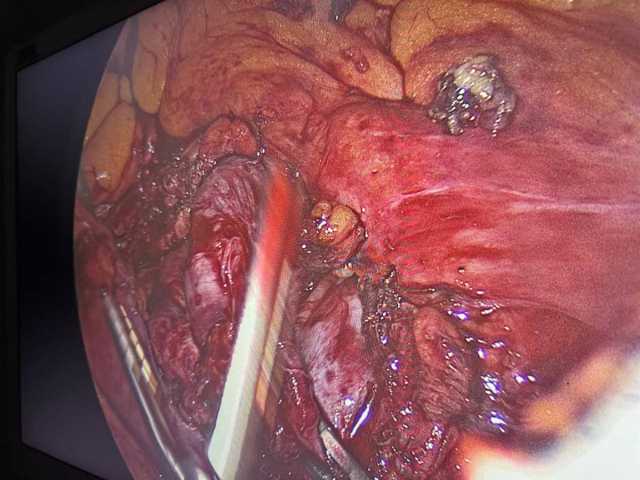

تمكن فريق طبي بقسم الجراحة العامة بمستشفى جامعة الأزهر بأسيوط من إجراء عملية جراحية دقيقة باستخدام المنظار لاستئصال كيس مساريقي كبير خلف الغشاء البريتوني لمريض يبلغ من العمر 43 عامًا، كان يعاني من آلام مزمنة بالبطن منذ نحو عام.

حيث أظهرت الفحوصات الطبية والأشعة المقطعية وجود كيس بحجم 6×7 سم بالجانب الأيسر من البطن يُشتبه في كونه كيسًا مساريقيًا (Mesenteric cyst)، وتم بفضل الله استئصاله بالكامل باستخدام المنظار الجراحي، بعد استكشاف البطن وتحديد موضع الكيس بدقة خلف الغشاء البريتوني، وقد تمت العملية بنجاح تام دون أي مضاعفات.